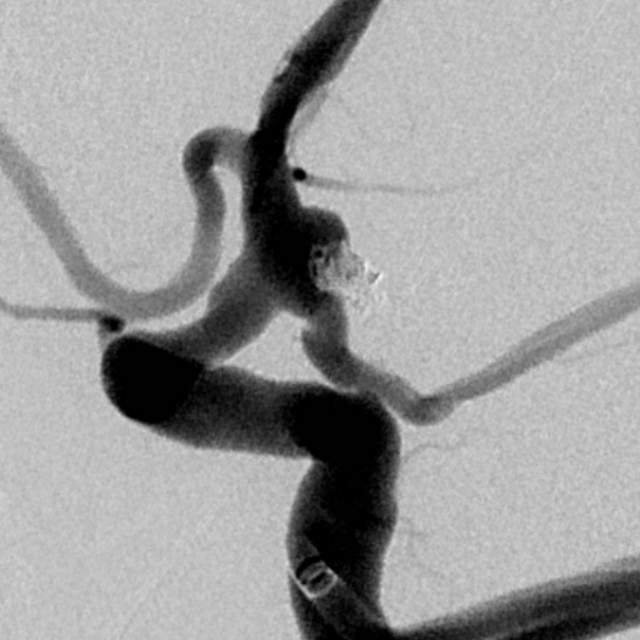

山东老年女性,2个月前遭遇颅内动脉瘤(一个血管上的不定时炸弹,不知道啥时候就爆炸了)破裂出血,病情危重。

动脉瘤经过多年修炼,形态奇葩,大动脉瘤上长着小动脉瘤,小动脉瘤上长着微小动脉瘤,还累及粗大的胚胎型大脑后动脉,经过一期单纯栓塞,消除了出血风险,老人家顺利出院康复。

近日,老人家恢复了差不多了,为了防治日后宽颈的脑动脉瘤复发,还需要稍微进行一下修修补补,减少血流对薄弱的脑动脉瘤的冲击,那就需要再简单加固一下。

这个加固的材料呢,放进血管后,慢慢会被自己的内皮细胞覆盖,变成自己身体的一部分,还能防止动脉瘤复发,是一个非常好的装备。

装备虽好,那还的找靠谱的医生给安装进去吧。今日,我们顺利为老人家在病变部位的血管植入了血流导向装置,手术顺利。然而,不是每一个破裂的脑动脉瘤患者像老人家一样这么幸运,能够有机会赶到医院,得到及时的治疗……